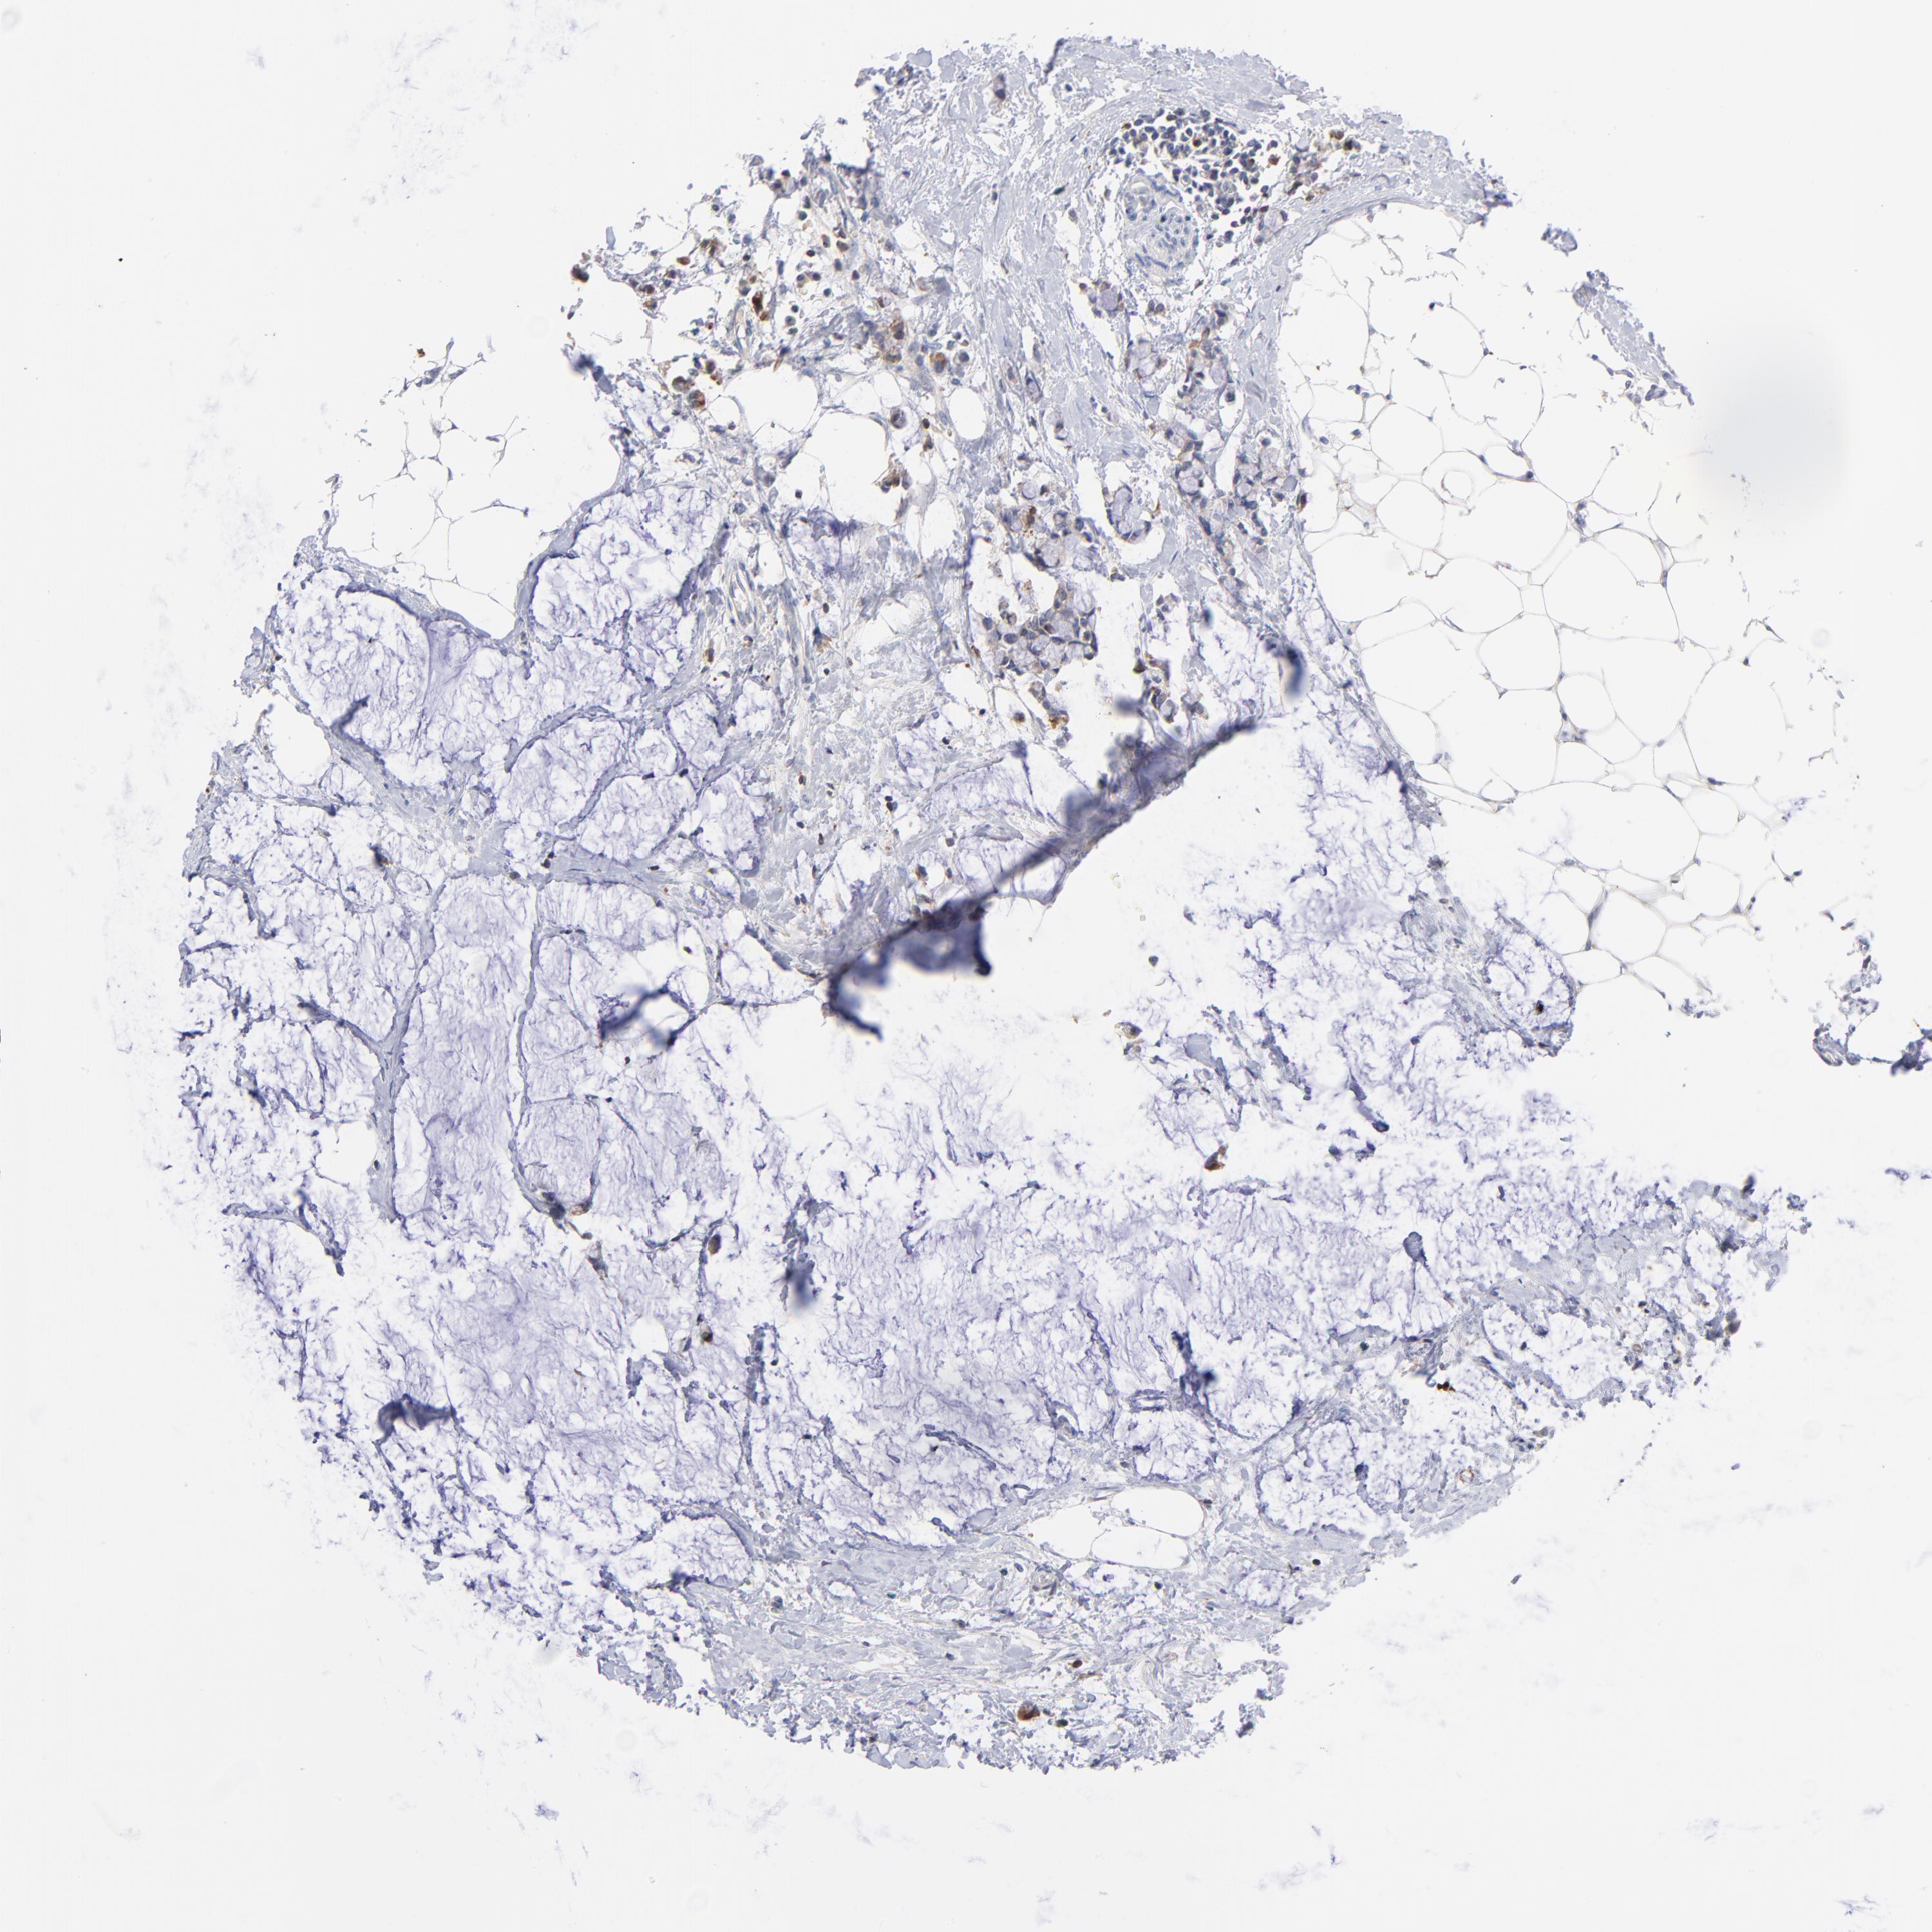

ANTIBODIES

AND

VALIDATION